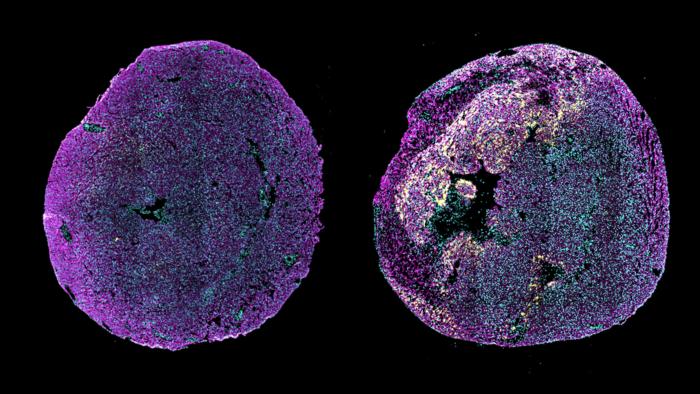

Immunofluorescence image of transverse heart sections from a healthy neonatal mouse (left) or a neonatal mouse in which myocardial infarction was induced at postnatal day 1, examined 3 days after injury (right). The yellow signal shows high levels of pro-ANP expression in the border region of the injured myocardium. Pro-ANP is an injury-responsive protein that helps promote cardiac repair in neonatal mice. Cardiomyocytes are shown in magenta (α-actinin) and cell nuclei are shown in cyan. Credit: Cheng Lab/Columbia University.